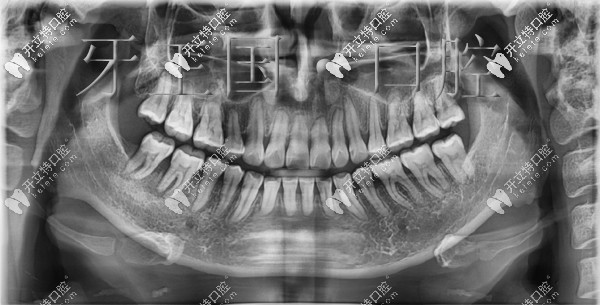

口腔X線片圖